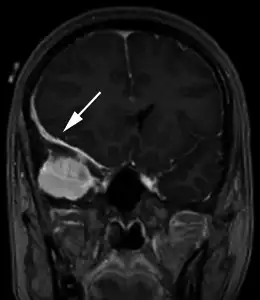

辐射对人体的伤害往往需要数年甚至数十年才能显现。在以色列的头癣受害者中,最早的癌症病例出现在1960年代末。1974年,以色列流行病学家巴鲁克·莫丹在《柳叶刀》杂志发表了一项开创性研究,追踪了约一万名在1950年代接受过头癣治疗的儿童。研究发现,与普通人群相比,这些儿童在成年后患头颈部肿瘤的风险显著增加——甲状腺癌的风险高出三倍,脑膜瘤的风险高出四倍,唾液腺癌的风险高出七倍。

莫丹的研究引发了医学界的广泛关注,也促使以色列政府开始正视这个问题。后续的研究进一步证实了辐射的长期危害。甲状腺是儿童辐射暴露后最易受影响的器官,因为甲状腺组织对辐射高度敏感,而儿童的甲状腺正处于快速发育阶段。接受过头癣治疗的儿童,其甲状腺癌发病率是普通人群的十八倍。更令人担忧的是,这些癌症往往在患者三十至五十岁时才被诊断,错过了最佳治疗时机。

脑膜瘤是另一种常见的辐射后遗症。这是一种起源于脑膜的良性肿瘤,生长缓慢但可能压迫大脑,导致头痛、癫痫和认知功能障碍。研究显示,儿童时期接受过头癣治疗的人,其脑膜瘤的发病率是普通人群的四倍以上。一些患者在几十年后才被发现脑中长有肿瘤,而此时肿瘤已经巨大,手术风险极高。